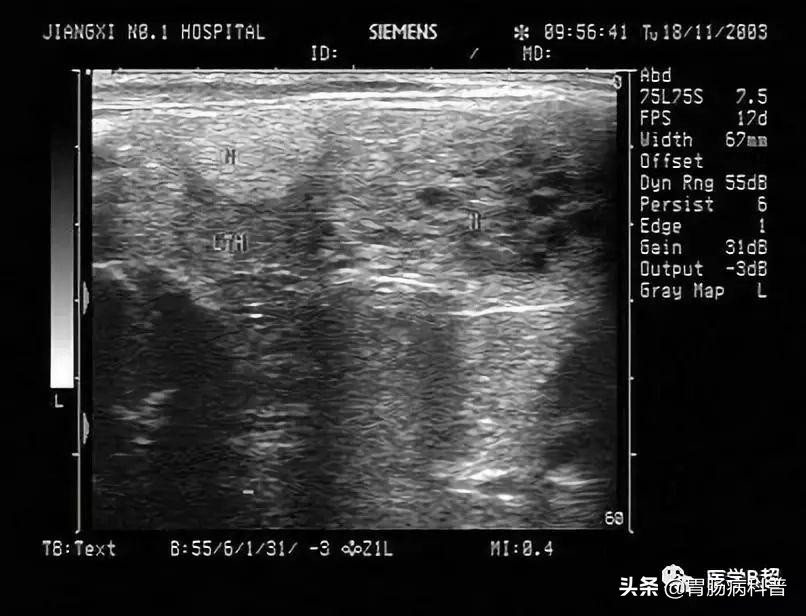

3.甲状腺超声检查

高清晰甲状腺超声检查是评价甲状腺结节最敏感的方法。它可判别甲状腺结节性质,如结节的位置、形态、大小、数目、结节边缘状态、内部结构、回声形式、血流状况和颈部淋巴结情况。对甲状腺囊肿性结节具有可靠诊断价值。也可用于超声引导下FNAC检查。